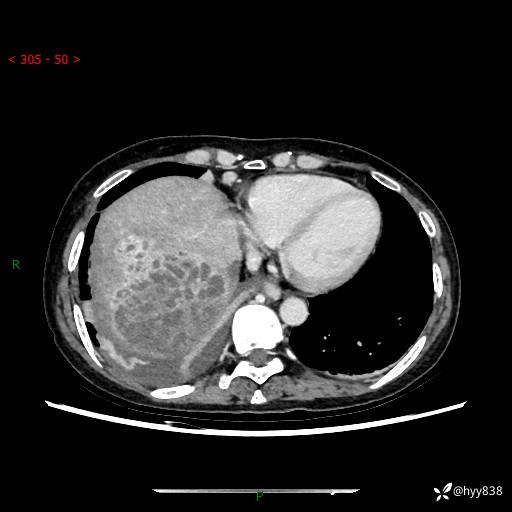

病例老年女性,发热来诊。如此“蜂窝煤”,治疗很棘手---结果公布~

性别:女

年龄:53岁

简要病史:发热(门诊急诊患者)

上腹部CT平扫